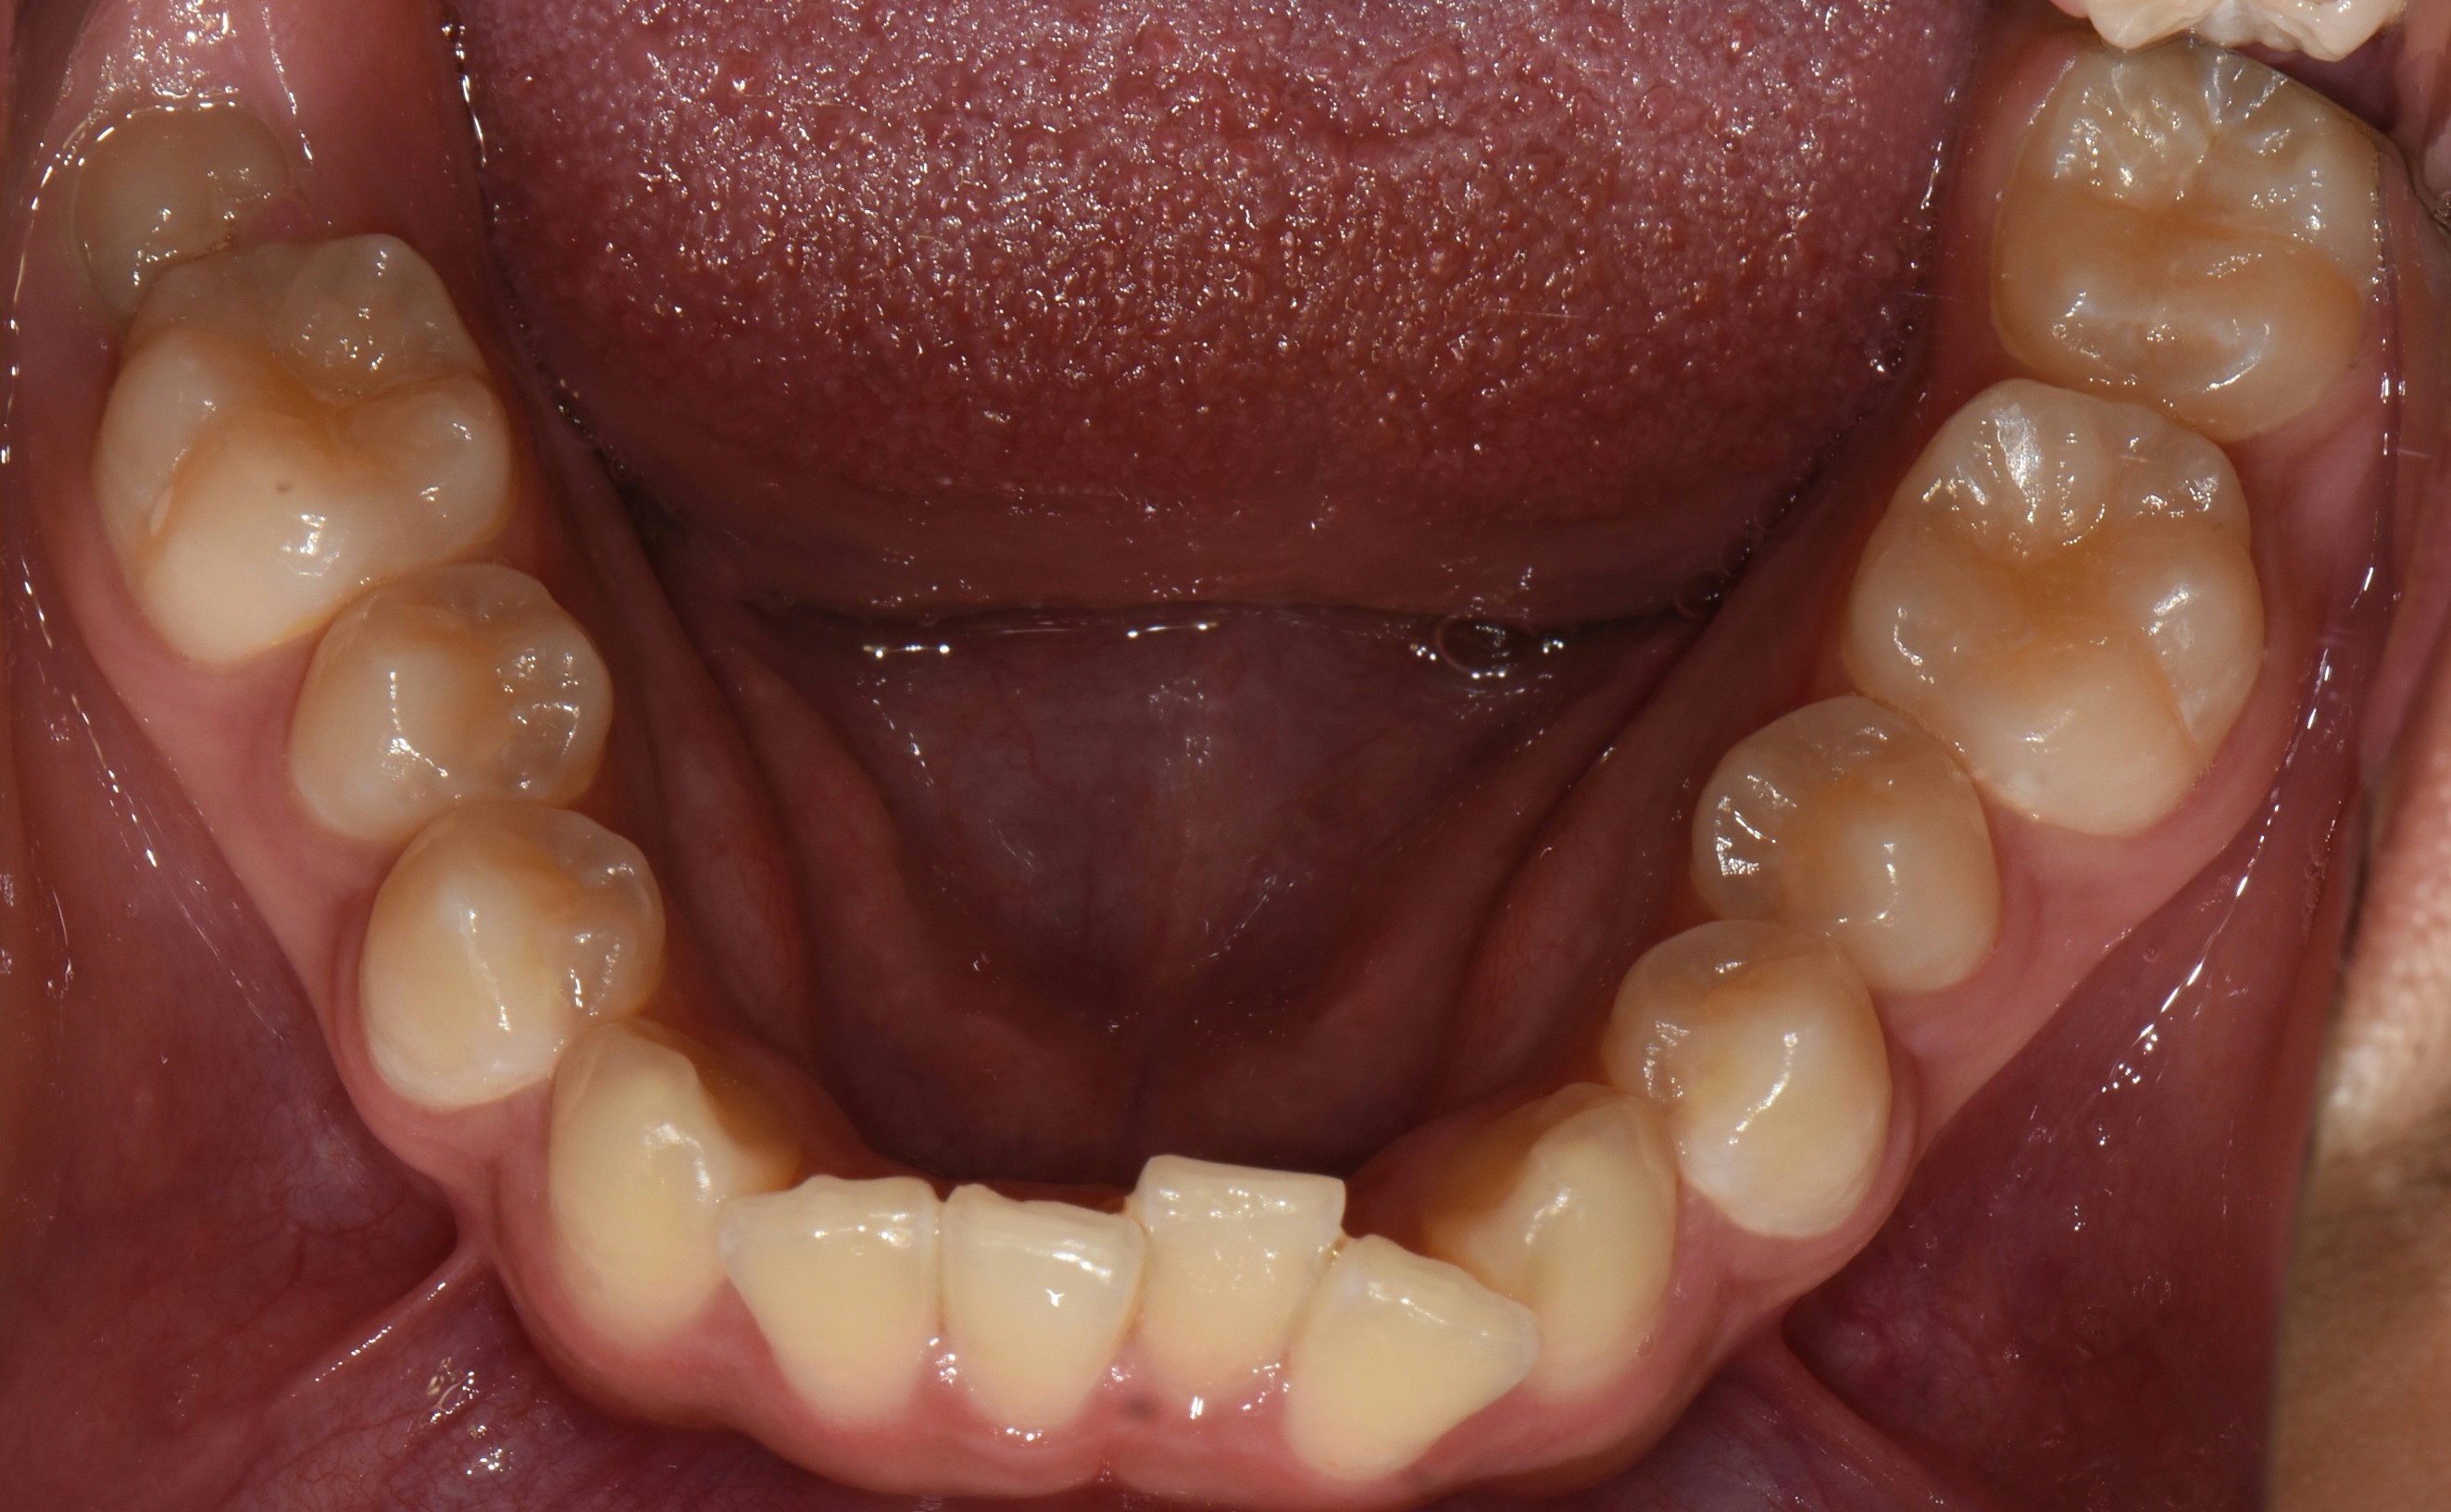

치료 전 사진입니다.